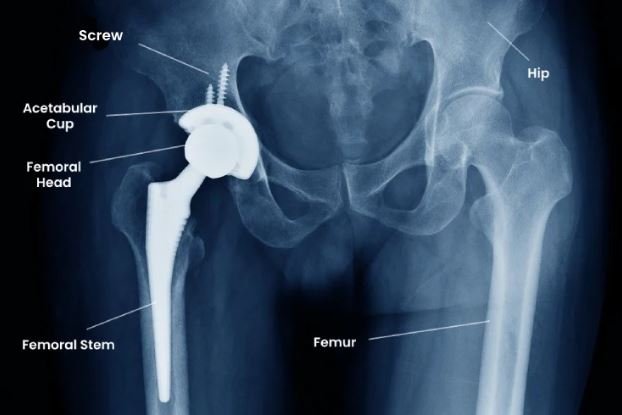

Total hip replacement surgery involves replacing the damaged hip joint with a prosthetic implant to restore mobility and reduce pain. Dr. Ponnanna K.M explained that the procedure is typically recommended when conservative treatments such as medication, physiotherapy, and lifestyle modification fail to provide relief.